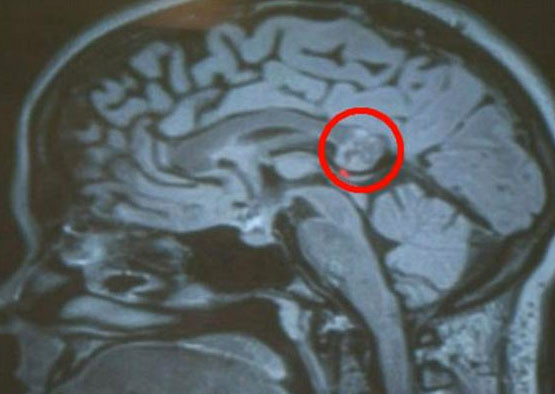

Beyninde tümör olduğu için ameliyata alınan 26 yşaındaki kızın aslında ikizini beyninde taşıdığı ortaya çıktı.

İkizi beyninde büyüdü - Resim: 1

Yapılan incelemeler sonrasında tümörün alınmasına karar veren cerrahlar Yamini'nin beynini açtığında ve tümör sandıkları şeyi çıkardıklarında şaşkına uğradı.

Cerrahlar Yamini'nin beynindekinin kemik, saç ve dişleri olan embriyonik bir ikiz yani teratom olduğunu keşfetti.